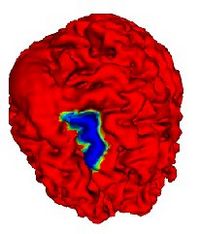

Soft Plaque Detection in CTA ImageryThe ability to detect and measure non-calcified plaques (also known as soft plaques) may improve physicians’ ability to predict cardiac events. This work automatically detects soft plaques in CTA imagery using active contours driven by spatially localized probabilistic models. Plaques are identified by simultaneously segmenting the vessel from the inside-out and the outside-in using carefully chosen localized energies More... New: Soft Plaque Detection and Automatic Vessel Segmentation. PMMIA Workshop in MICCAI, Sep. 2009. |